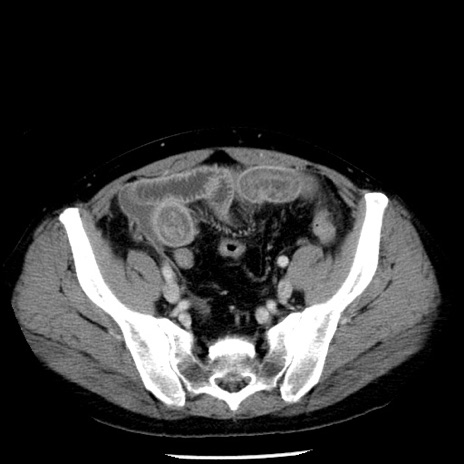

症例29(横断像)

【症例】40歳代男性

【現病歴】2日前から胃痛あり。徐々に周期的な激痛に変化した。本日になっても激痛があるため受診。

【身体所見】意識清明、BT 38-39℃台あり、腹部:膨満、やや硬、右下腹部に圧痛あり。

【データ】WBC 8500、CRP 23.26